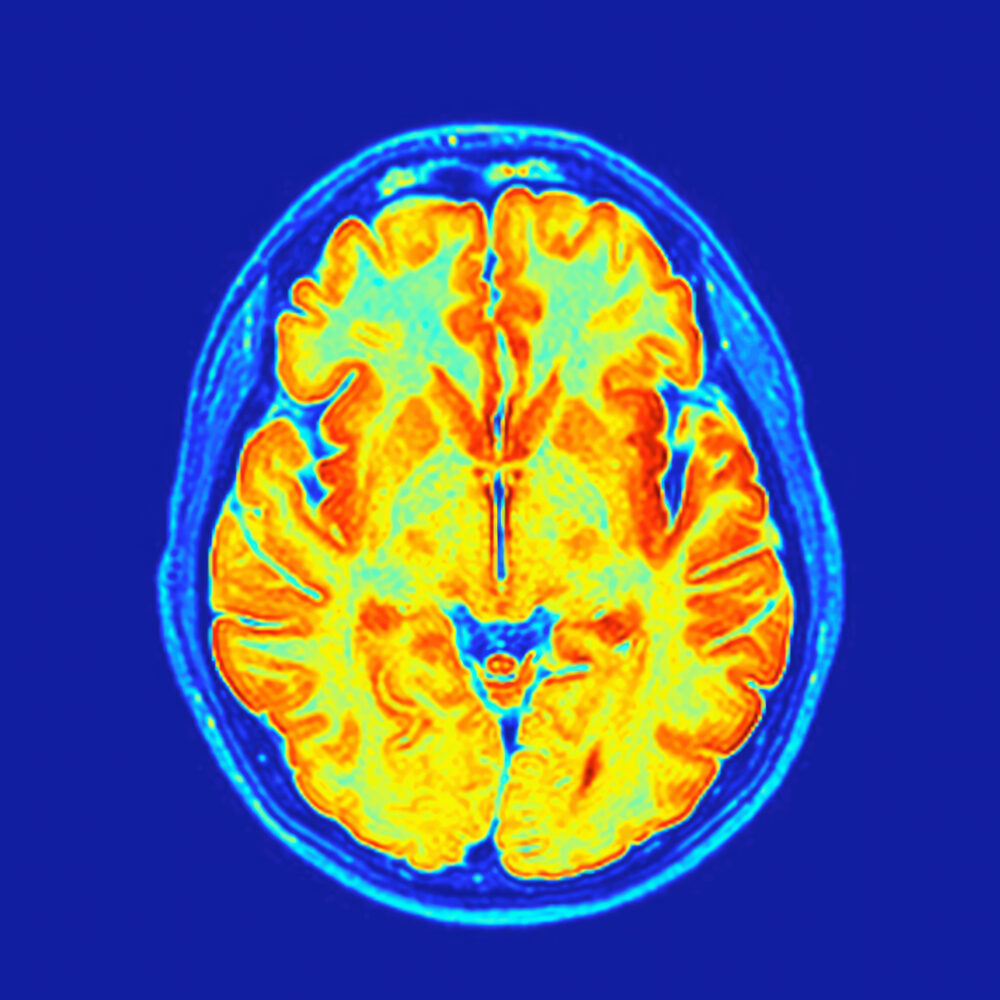

When University of Virginia neuroscientist Harald Sontheimer shared this year’s International Prize for Translational Neuroscience with Stanford’s Michelle Monje, publicity about the award created the impression of a partnership. The two were credited with the potentially life-saving and, thus, marketable discovery that gliomas—deadly brain tumors—wire themselves into neural networks, hijacking brain activity to fuel their […]